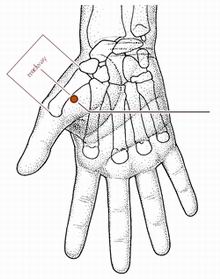

鱼际穴

经穴名。出《灵枢·本输》属手太阴肺经。荥(火)穴。在手拇指本节(第一掌指关节)后凹陷处,约当第一掌骨中点桡侧,赤白肉际处。布有桡神经浅支和从拇指流向头静脉的小静脉支。主治咳嗽,咯血,咽喉肿痛,发热,及扁桃体炎,小儿营养不良等。直刺0.5-1寸。艾炷灸1-3壮;或艾条灸3-5分钟。